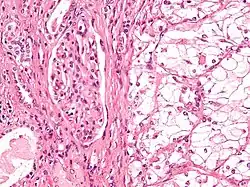

| Micrograph showing the most common type of kidney cancer (clear cell renal cell carcinoma). H&E stain. | |